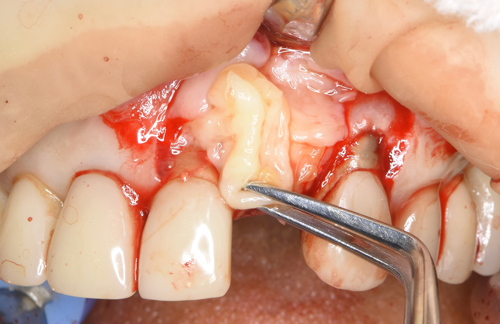

増設した人工の骨をより定着させるために、血液から作ったコラーゲン膜を何層にも敷き詰めていきます(無料)。あとは仮歯を施して、骨が固定するのを6ヶ月間待ちます。

①抜歯と②インプラントの移植と③欠落した骨の再生の3つを1日で完結させました。通常なら2年近くかかる治療内容を当院では半分で終わらせる事に注力しています。